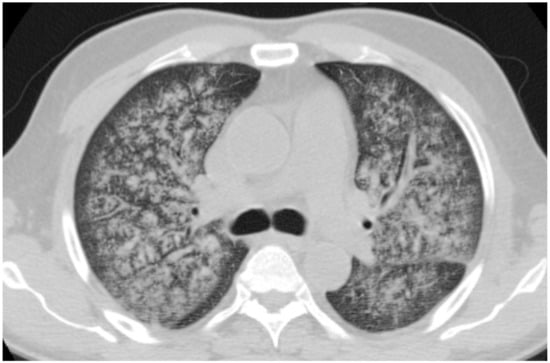

2.10.2. Morphological Patterns and Imaging

| MPA | GGOs due to hemorrhagic alveolitis (common); consolidation, nodules with centrilobular distribution (less common) |